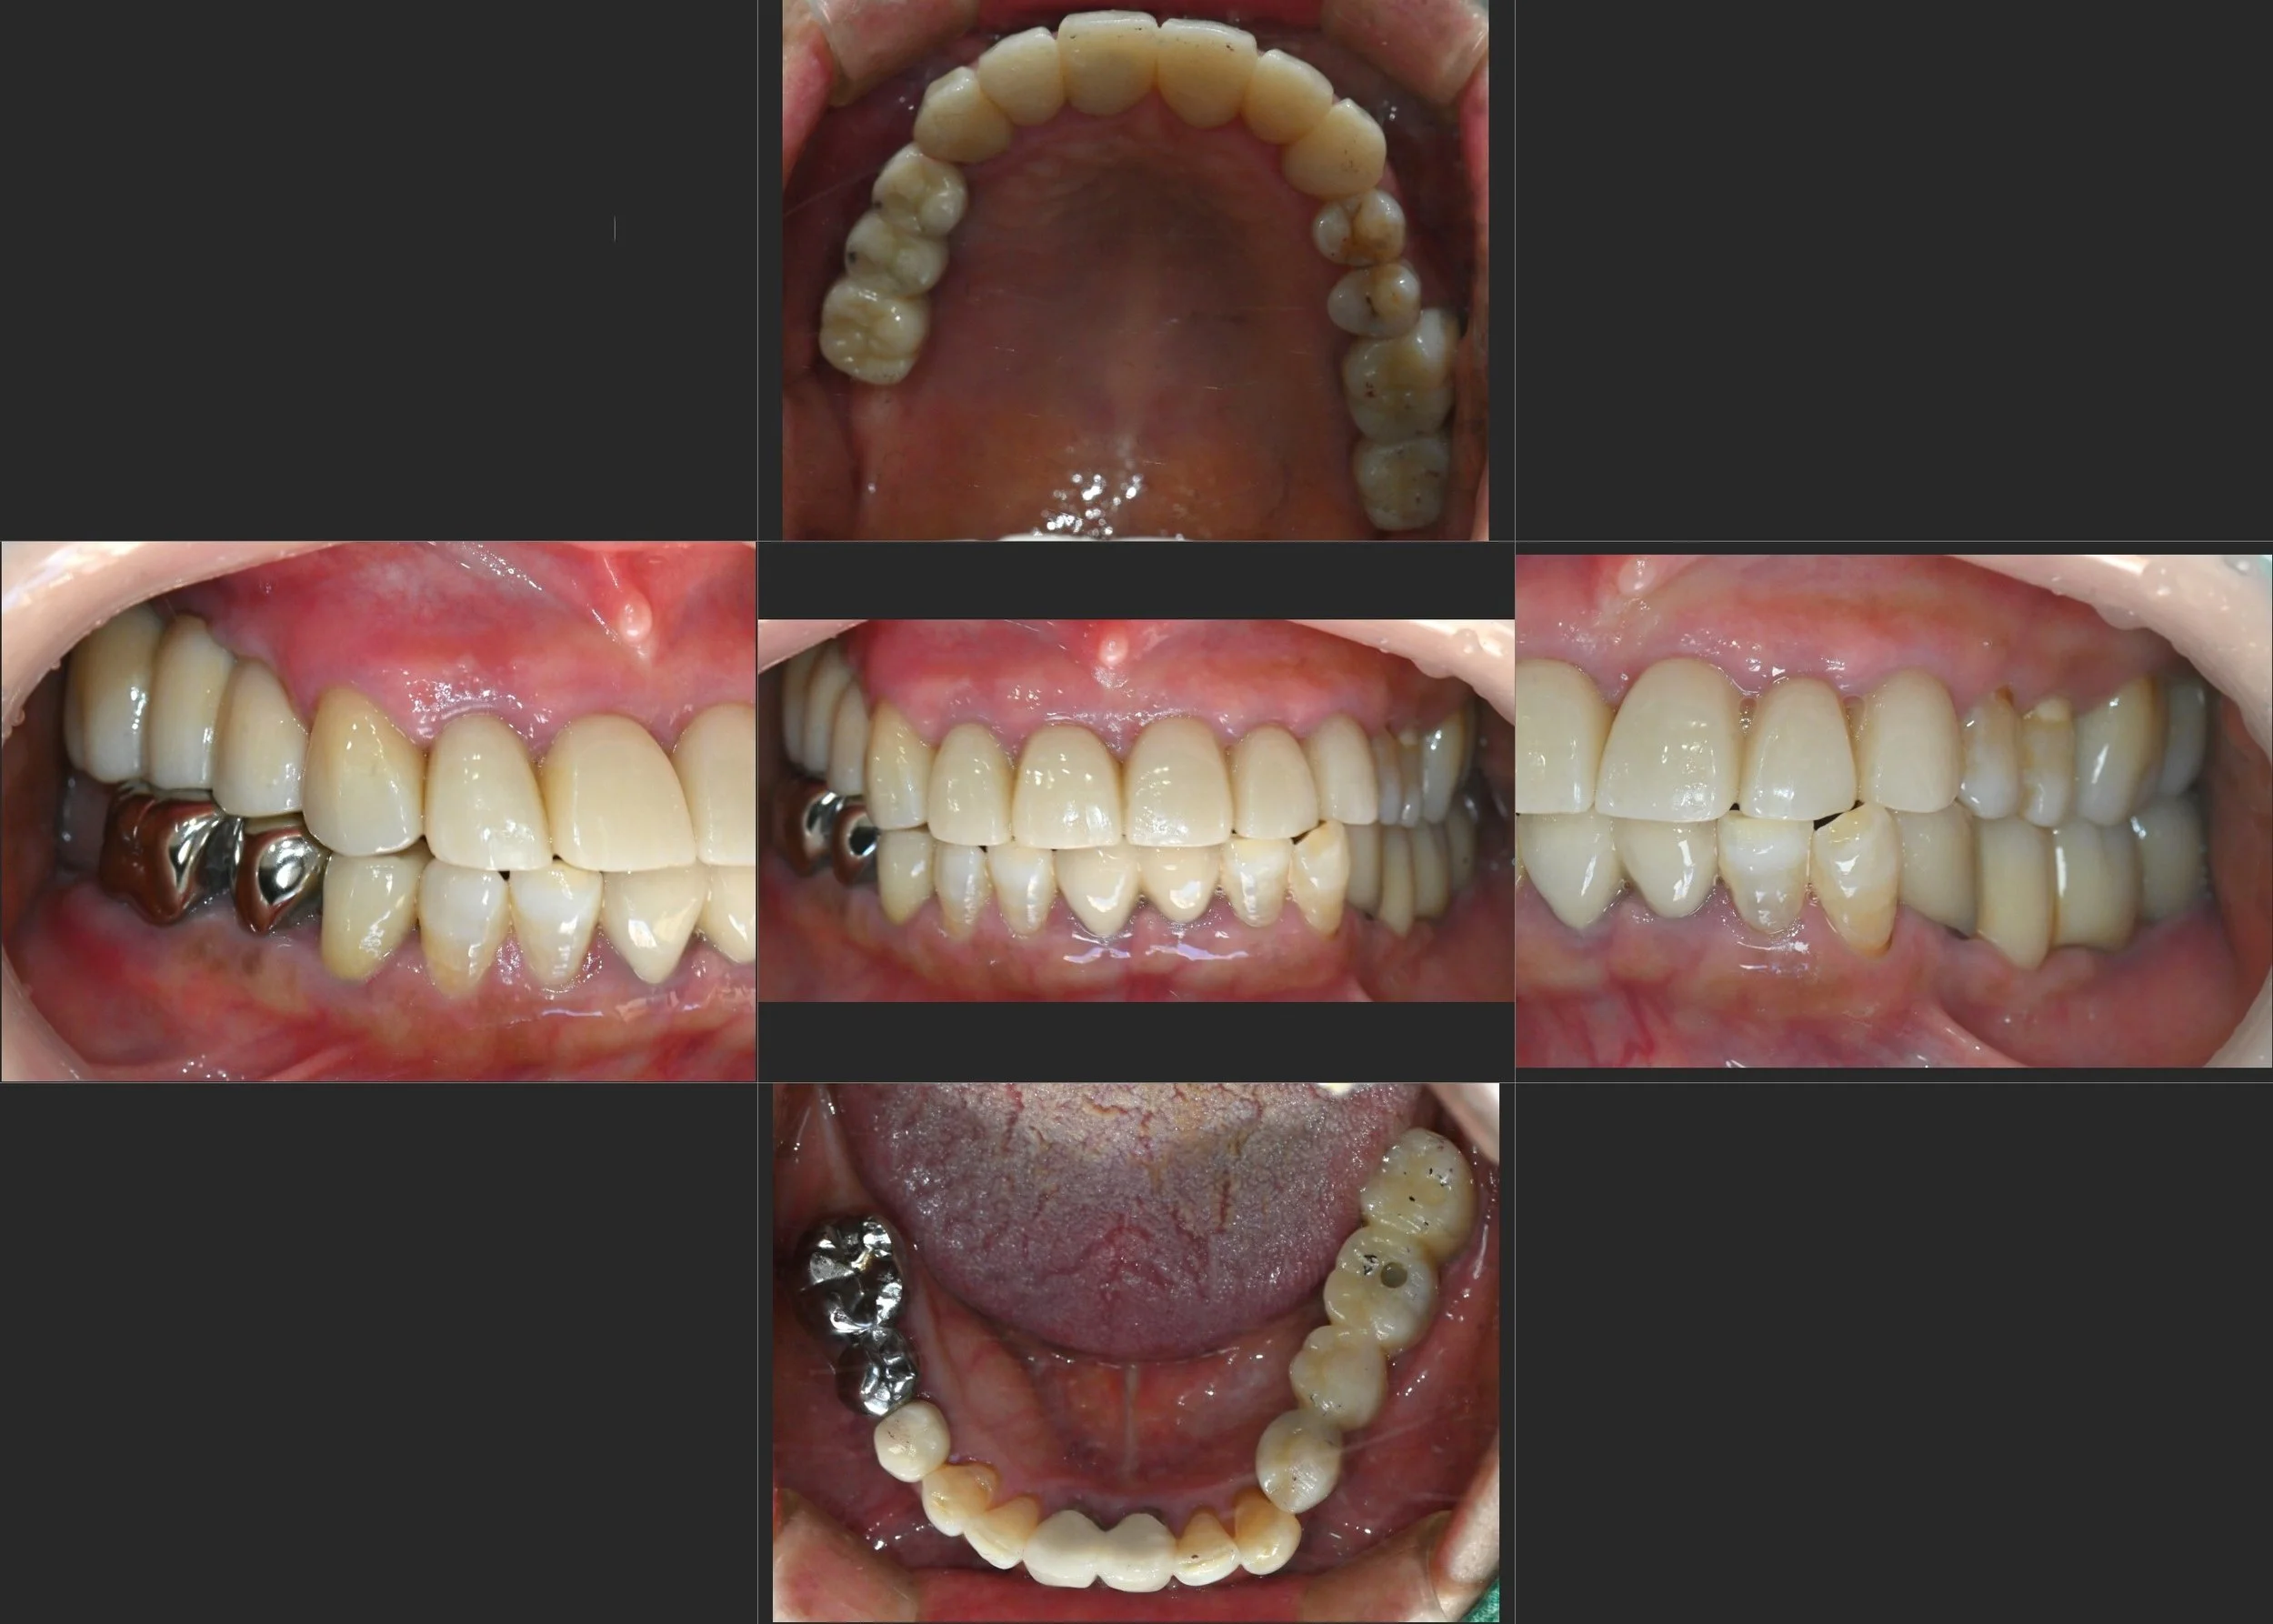

INTRA ORAL - BEFORE